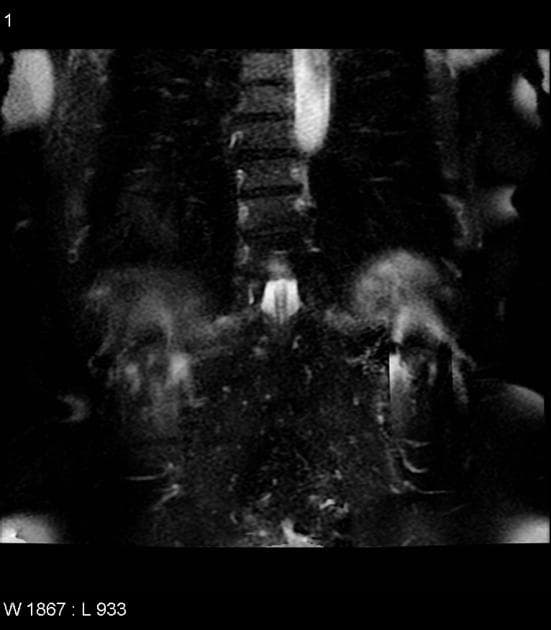

Coronal C+ portal venous phase

CT•Coronal C+ portal venous phase•1 / 159

- Trên pha tĩnh mạch cửa, tổn thương vẫn duy trì tỷ trọng mỡ, viền tăng tỷ trọng còn tồn tại, kèm theo vân hóa mỡ xung quanh; không thấy hình thành áp xe (abscess), không thấy túi thừa (diverticula) ở đại tràng kế cận, thành manh tràng bình thường.